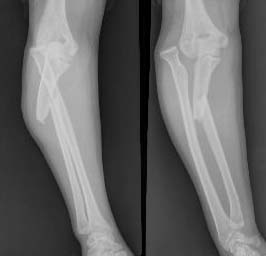

标题: X4207:看看这个骨折片,是不是很典型!

孟氏骨折:尺骨上1/3骨折合并桡骨头脱位。1914年意大利外科医生monteggia最早报导了这种类型骨折,故称孟氏骨折。分三种类型(一)伸直型   比较常见,多发生儿童。肘关节伸直或过伸位跌倒,前臂旋后掌心触地。作用力顺肱骨传向下前方,先造成尺骨斜形骨折,残余暴力转移于桡骨上端,迫使桡骨头冲破,滑出环状韧带。向前外方脱位。骨折断端向掌侧及桡侧成角。成人直接暴力打击造成骨折,骨折为横断或粉碎型。

(二)屈曲型   多见于成人。肘关节微屈曲,前臂旋前位掌心触地,作用力先造成尺骨较高平面横型或短斜型骨折,桡骨头向后外方脱位,骨折断端向背侧,桡侧成角。

(三)内收型   多发生幼儿。肘关节伸直,前臂旋前位,上肢略内收位向前跌倒,暴力自肘内方推向外方,造成尺骨喙突处横断或纵行劈裂骨折,移位较少,而桡骨头向外侧脱位。